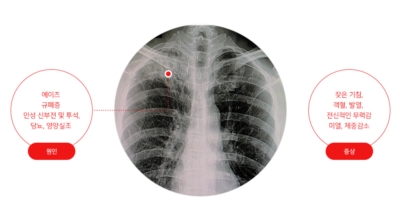

흉부 엑스레이

엑스레이 검사 방법으로는 실제 크기로 촬영하는 흉부 직접 촬영과 마이너스 70mm, 100mm 사진으로 촬영하는 간접 촬영이 있다고 하며, 일부 사람을 단체로 검사할 때 간접 촬영이 많이 활용돼요. 조사결과에 근거하면 결핵은 과감염성 결핵과 재활성성 결핵으로 구분되며, 기존 결핵은 소아결핵과 성인결핵으로 소속되는 경우가 많았어요. 인간면역결핍바이러스(HIV)에 감염된 사람들은 주로 과감염된 결핵을 보이 다고 알려져 있답니다.